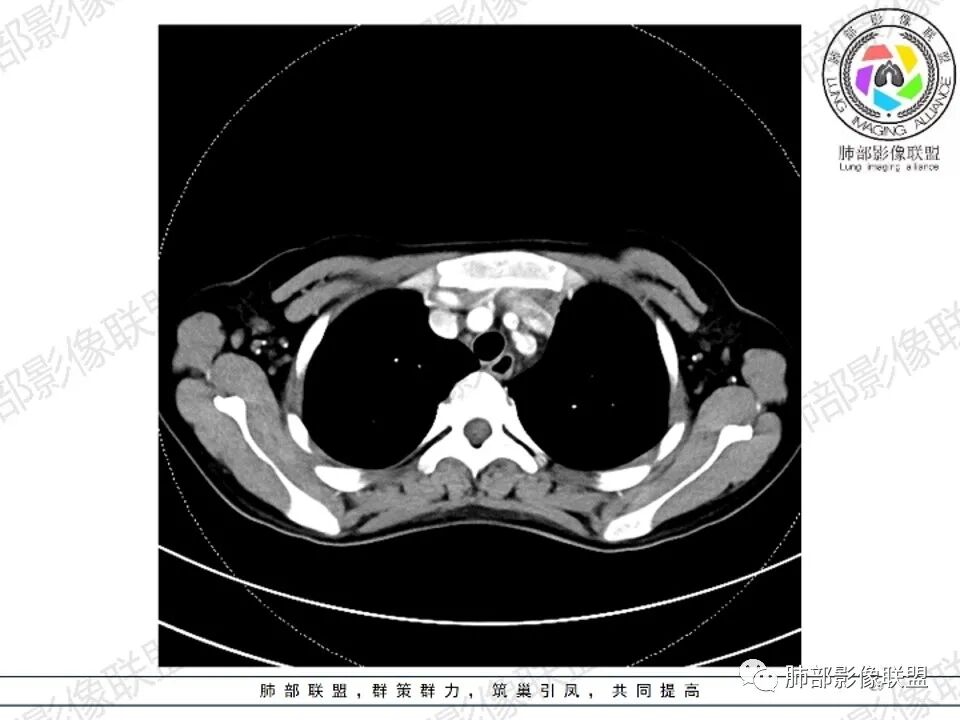

临床:年轻女性,慢性病程,多系统病变,头晕,贫血,视物模糊。

CT:定位纵膈病变,前中纵隔多发肿块,质软,塑形,密度不均匀,边界清楚。增强不均匀强化,坏死边界清楚,血管漂浮征。双侧腋下多组淋巴结肿大,明显异常强化。

考虑淋巴瘤可能。

鉴别诊断:系统性疾病,胸腺增生,胸腺瘤,胸腺癌